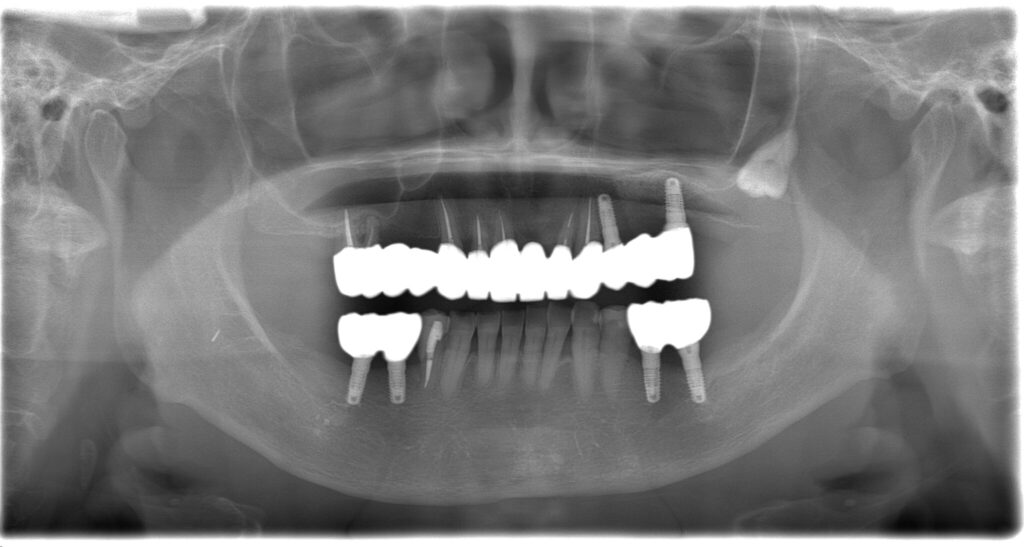

全顎治療症例

| 治療内容 | インプラント埋入(左下5・6,右下5・6,左上4・6) サイナスリフト(左上4・6) ジルコニアBr(右上6−左上3) E –MAX CAD(右下4) セラミックインレー(左下4) |

| 費用 | インプラント治療 約2,000,000円 その他被せ物治療など 約1,000,000円 合計 約3,000,000円 *いずれも税込 |

- 定期的なメインテナンスを行わない場合、インプラントが脱落する可能性があります。被せ物は経年的な劣化で欠ける可能性があります。